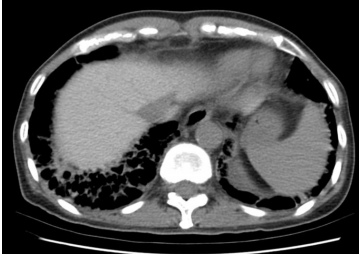

17. 63歲女性病人因風濕性心臟病換過二尖瓣瓣膜,心律不整長期使用藥物。因為喘的情形加劇,CXR及電腦斷層如圖示,下列何者為是? (A) 為典型的 Interstitial Lung Disease,可以是idiopathic pulmonary fibrosis。 (B) 肺部有許多小點,Miliary TB無法排除。 (C) X光及電腦斷層有許多的線條,可以是kerley line 應為肺水腫。 (D) 無顯影劑肝臟卻明顯較亮要考慮Amiodarone 造成的 Interstitial Lung Disease。 (E) 有許多的點跟線,應考慮肺癌合併 lymphangitis carcinomatosis。